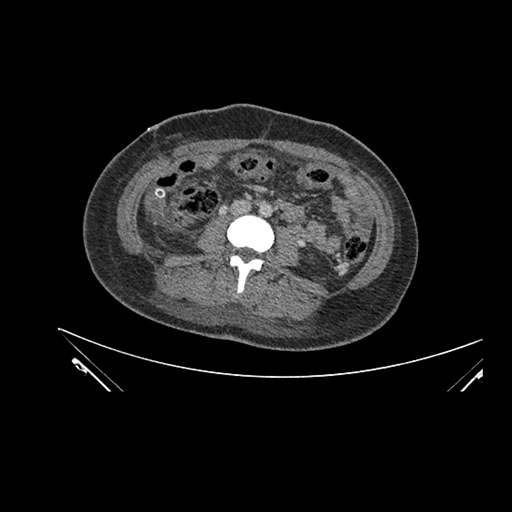

Axial Venous

Imaging analysis

Based on initial findings, which issue(s) would you be most concerned about?